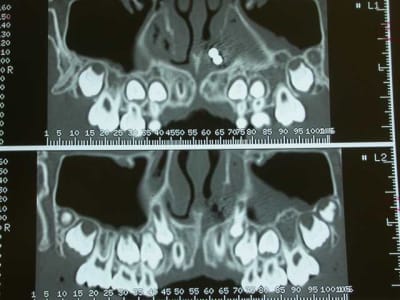

La maman de zoe vient en consultation, pour un contrôle semestrielle. Elle est enceinte de 8 mois, se porte bien , et rien de particulier ne doit être entrepris avant la fin de la grossesse. En fin de rendez-vous, elle me demande de jeter un œil sur Zoe. La petite agée de 9ans et demi présente une jolie classe III osseuse. J’en profite pour lui faire une panoramique. Là, à ce stade, vous avez tous vu le résultat. Je vérifie qu’il ne reste pas une barrette oubliée ou autre (nada), et préfère effectuer une nouvelle pano. Même résultat.

Je questionne l’ enfant et la maman. Personne ne se rappelle de rien. Je me renseigne s’il n’y a pas eu une intervention chirurgicale, et le seul antécédent est une opération pour ôter les végétations, il y a 4 ans. J’examine le nez et ne vois rien. Je pense plus à un objet oublié pendant l’intervention.

Je décide donc de faire réaliser un scanner et là c’est nouveau pour vous.

Une fois le scanner réalisé, je vois bien qu’il s’agit d’un objet composé de boules et l’adresse illico à son orl. Il la reçoit dans la foulée, et au vu du scanner, se refuse d’intervenir de peur de renvoyer plus loin l’objet. A son tour, il l’adresse à un hopital spécialisé enfants (Robert Debré). Au service ORL, ils tentent de retirer l’objet avec une pince (comme Dr House le faisait dans un épisode) et rien de neuf, aucune progression.